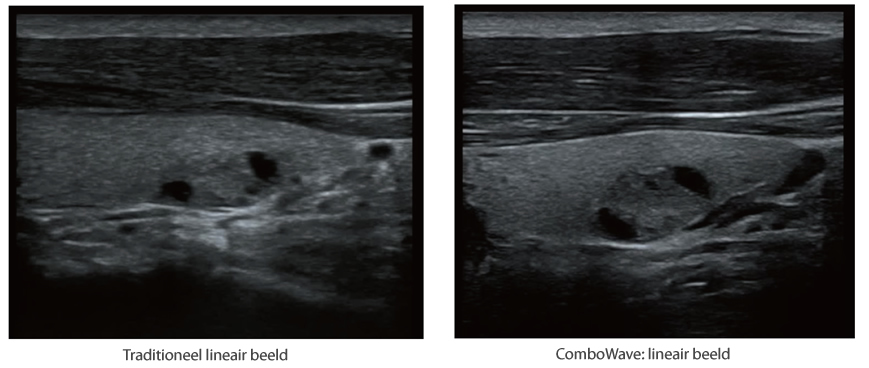

ComboWave transducers

In tegenstelling tot traditionele transducers gebruiken de ComboWave-transducers een nieuw type samengesteld piëzo-elektrisch materiaal om het akoestische spectrum drastisch te optimaliseren en de akoestische impedantie te verminderen. De lineaire transducers van ComboWave, die verder zijn geïntegreerd met de unieke 3T-technologie van Mindray, stellen u in staat uitstekende prestaties te ervaren met een extreem hoge beeldresolutie en uniformiteit in de schildklier, borst, vaten en meer.